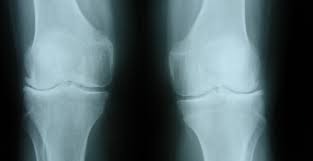

HOMOEOPATHIC REMEDIES FOR OSTEITIS

Inflammation of bones

Causes—Polyostotic fibrous dysplasia, SAPHO syndrome, Paget’s disease of bone, osteitis  fibrosa cystica, osteitis condensans

Symptoms –Bone pains , joint stiffness